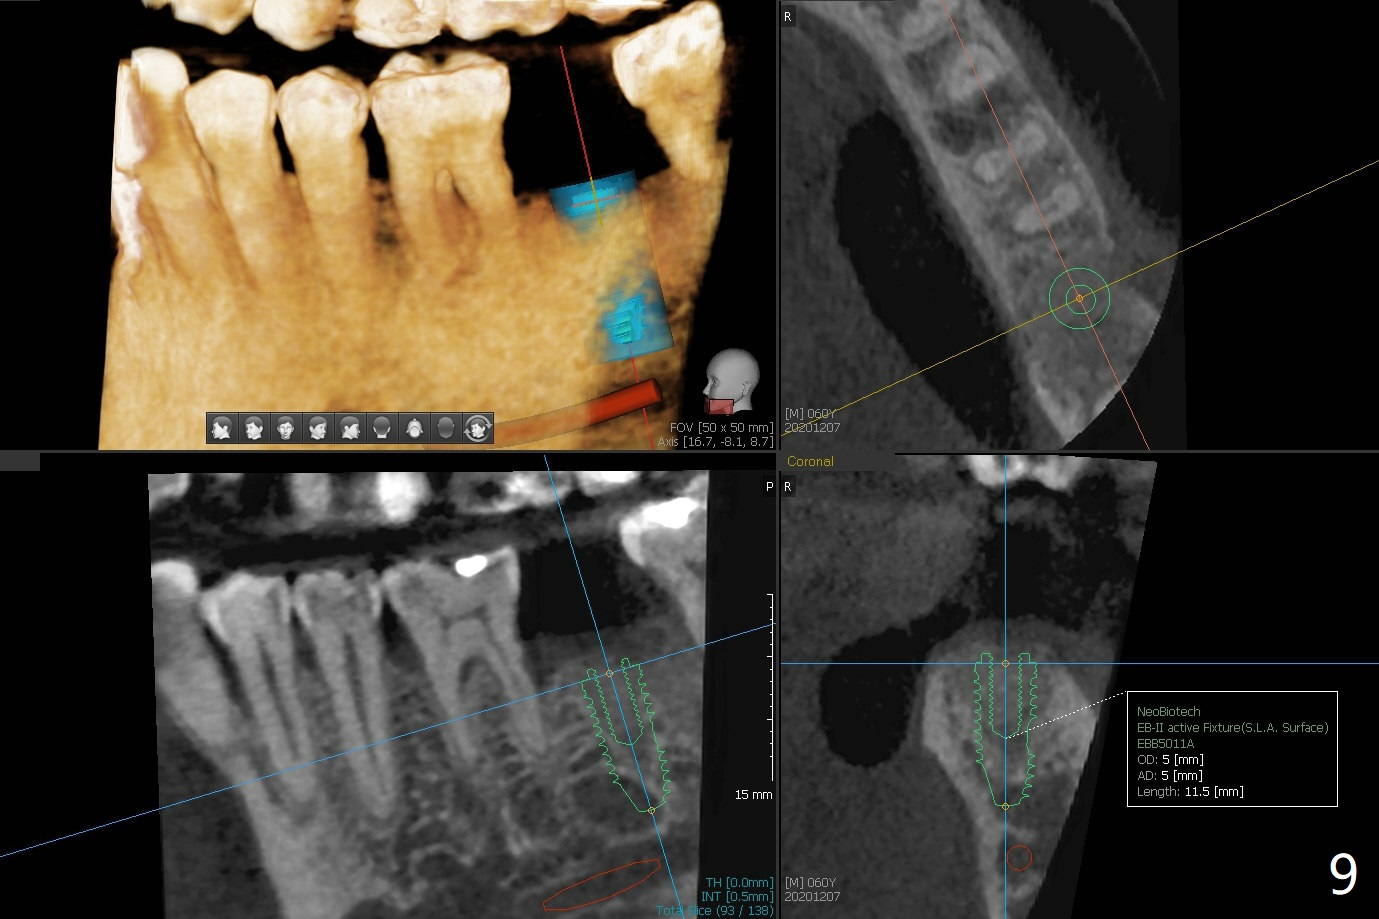

60岁男,吸烟,口腔卫生不好,不积极配合治疗,下前牙两个植体螺纹暴露,但是没有症状。两年中,左下七(图一,二)不能保留(图三),虽然六远中结石被清除(图三>),七位点保留(图四 *)时未能顺便在六远中填入骨粉(用血混合,胎盘膜覆盖)。四五个月后,七种植时将钻头骨粉放置于六远中缺损处,如何才能让骨粉在患处生根发芽?术后一个月,去除树脂敷料后,最表面骨粉未能被整合,下面骨粉好像已经与肉芽组织结合了(图五),其实根尖片应该拍摄证实这一点。吸烟者血供不好,愈合欠佳。术后三个月牙槽嵴宽(图六);高度稍微减低(图七)。术后4个月CT显示近中牙槽窝正好位于缺牙区正中(图八),所以植体必然进入近中窝(图九)。

完成钻洞后(图十),潜行分离(掀开)近中牙龈(图十一),去除6远中肉芽组织和结石(图十二),涂Endogain,放置粘性骨粉(图十三),最后放置植体。